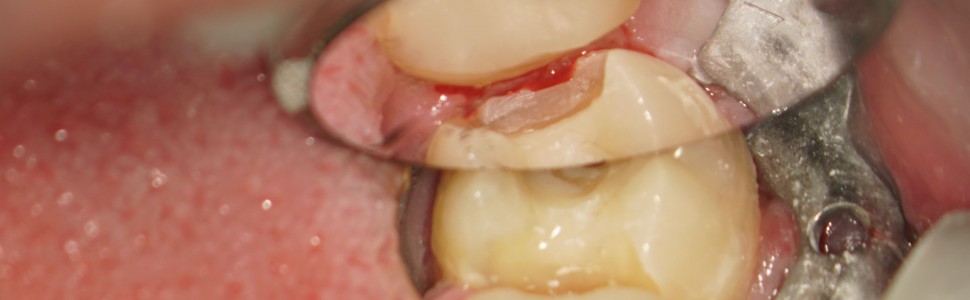

ARTYKUŁ Z FILMEM: Opis przypadku leczenia kanałowego zęba 37 z przewlekłym stanem zapalnym tkanek okołowierzchołkowych przy użyciu laserów Er:YAG i Nd:YAG oraz ponownego leczenia kanałowego zęba 36 z usunięciem złamanych narzędzi

Opis przypadku leczenia kanałowego zęba 37 oraz ponownego leczenia kanałowego zęba 36 z usunięciem złamanych narzędzi, z rozległym, przewlekłym zapaleniem tkanek okołowierzchołkowych z użyciem lasera Er:YAG (2940 nm) do wspomożenia procesu aktywacji roztworów płuczących oraz lasera Nd:YAG (1064 nm) w celu dezynfekcji głębszych struktur zębinowych, wraz z rekonstrukcją korony jako przygotowanie do dalszego leczenia protetycznego. W leczeniu zęba 37 zastosowano zachowawcze podejście do usuwania twardych tkanek zęba (tak zwane Truss Access), którego bezpieczne i przewidywalne wykorzystanie uwarunkowane było zastosowaniem lasera Er:YAG podczas procedur płukania komory i systemu kanałowego. Zastosowanie powyższego urządzenia pomogło i znacząco przyspieszyło proces usunięcia złamanych narzędzi z zęba 36 dzięki wykorzystaniu tak zwanej fali uderzeniowej (shockwave) wywołanej przez efekt fotoakustyczny (photon induced photoacoustic streaming).

Description of the case of root canal treatment of tooth 37 and re-treatment of tooth 36 with the removal of broken instruments, with extensive, chronic inflammation of the periapical tissues with the use of the Er:YAG laser (2940 nm) to support the activation process of rinsing solutions and the Nd: YAG laser (1064 nm) to disinfect the deeper ones dentin structures, along with the reconstruction of crown structures as a preparation for further prosthetic treatment. In the treatment of tooth 37, a conservative approach to the removal of hard tooth tissues (the so-called Truss Access) was used, the safe and predictable use of which was conditioned by the use of the Er:YAG laser during the rinsing procedures of the chamber and the canal system. The use of the above device helped and significantly accelerated the process of removing broken tools from tooth 36 thanks to the use of the so-called Photon induced photoacoustic streaming.